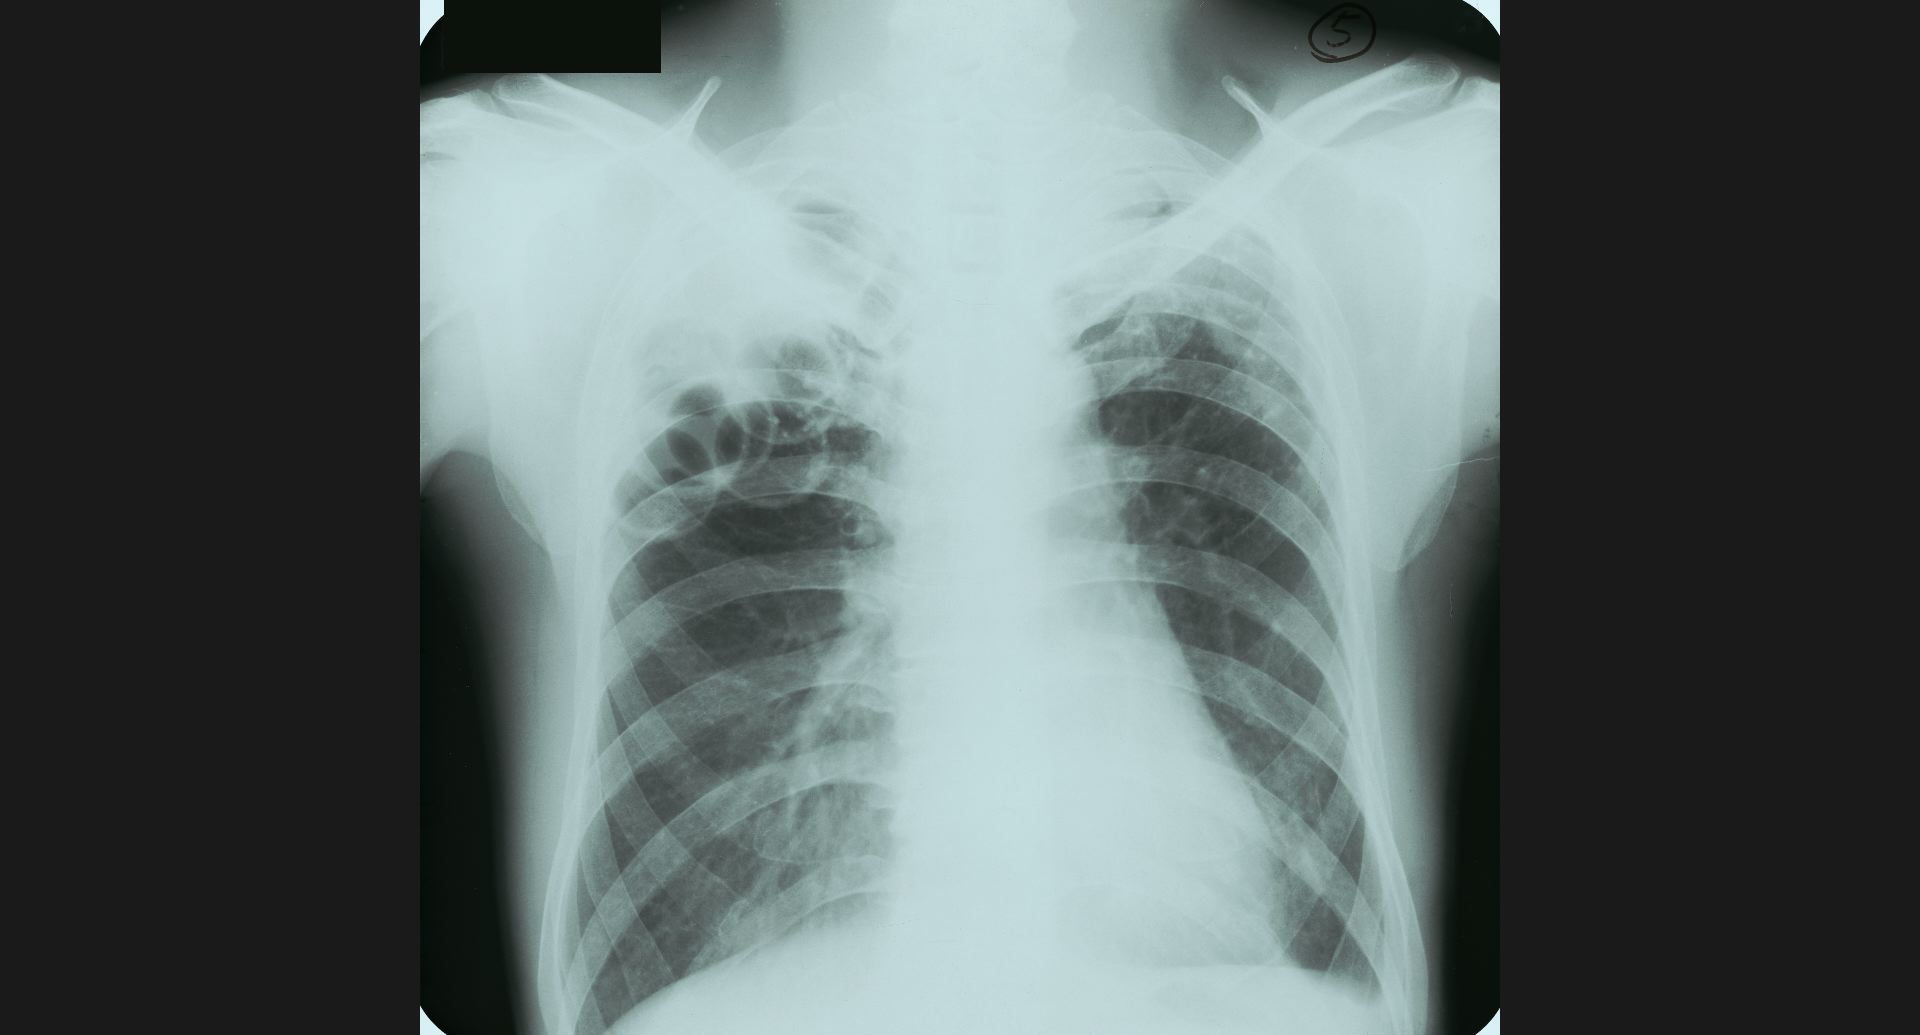

fig.1(117KB)

:Alveolar microlithiasis細かい肺病変、air bronchogram。